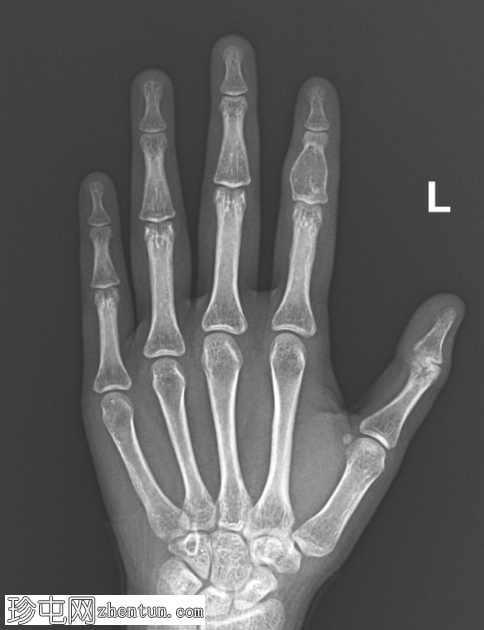

X线片

1.png

正位片

左手食指中节指骨可见一边界清晰、膨胀性髓内溶骨性病变。病变表现为骨内膜凹陷伴轻度皮质变薄,但未见皮质破裂。软骨基质钙化呈淡点状。未见骨膜反应或邻近软组织肿块。未见病理性骨折。邻近的近节和远节指间关节结构完整。其余可见骨骼密度和排列正常,未见其他病变。